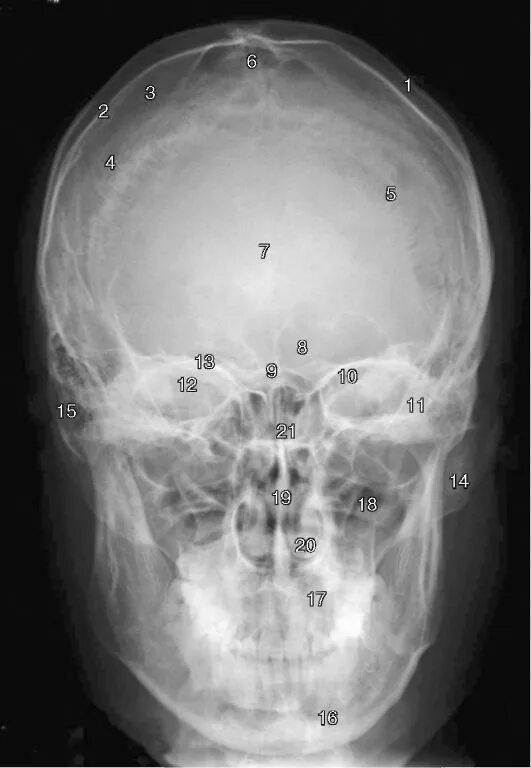

Проекции рентгенограмм черепа